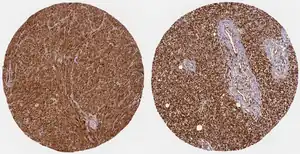

WWTR1 (TAZ) is implicated a wide variety of cancers including melanoma, head and neck squamous cell carcinoma, breast cancer, non-small cell lung cancer, and others due to its high gene and histological expression, as well as correlation with increased metastasis and poorer survival in animal studies and patient data.[9] Along with the structurally similar co-regulator YAP, many studies have described their role in promoting oncogenesis, altering neoplastic metabolism, and generating resistance to therapeutic intervention.[8][9][32][33] In particular, TAZ overexpression conferred resistance to cisplatin chemotherapy as well as immunotherapy treatment with a PD-1 antibody.[32]